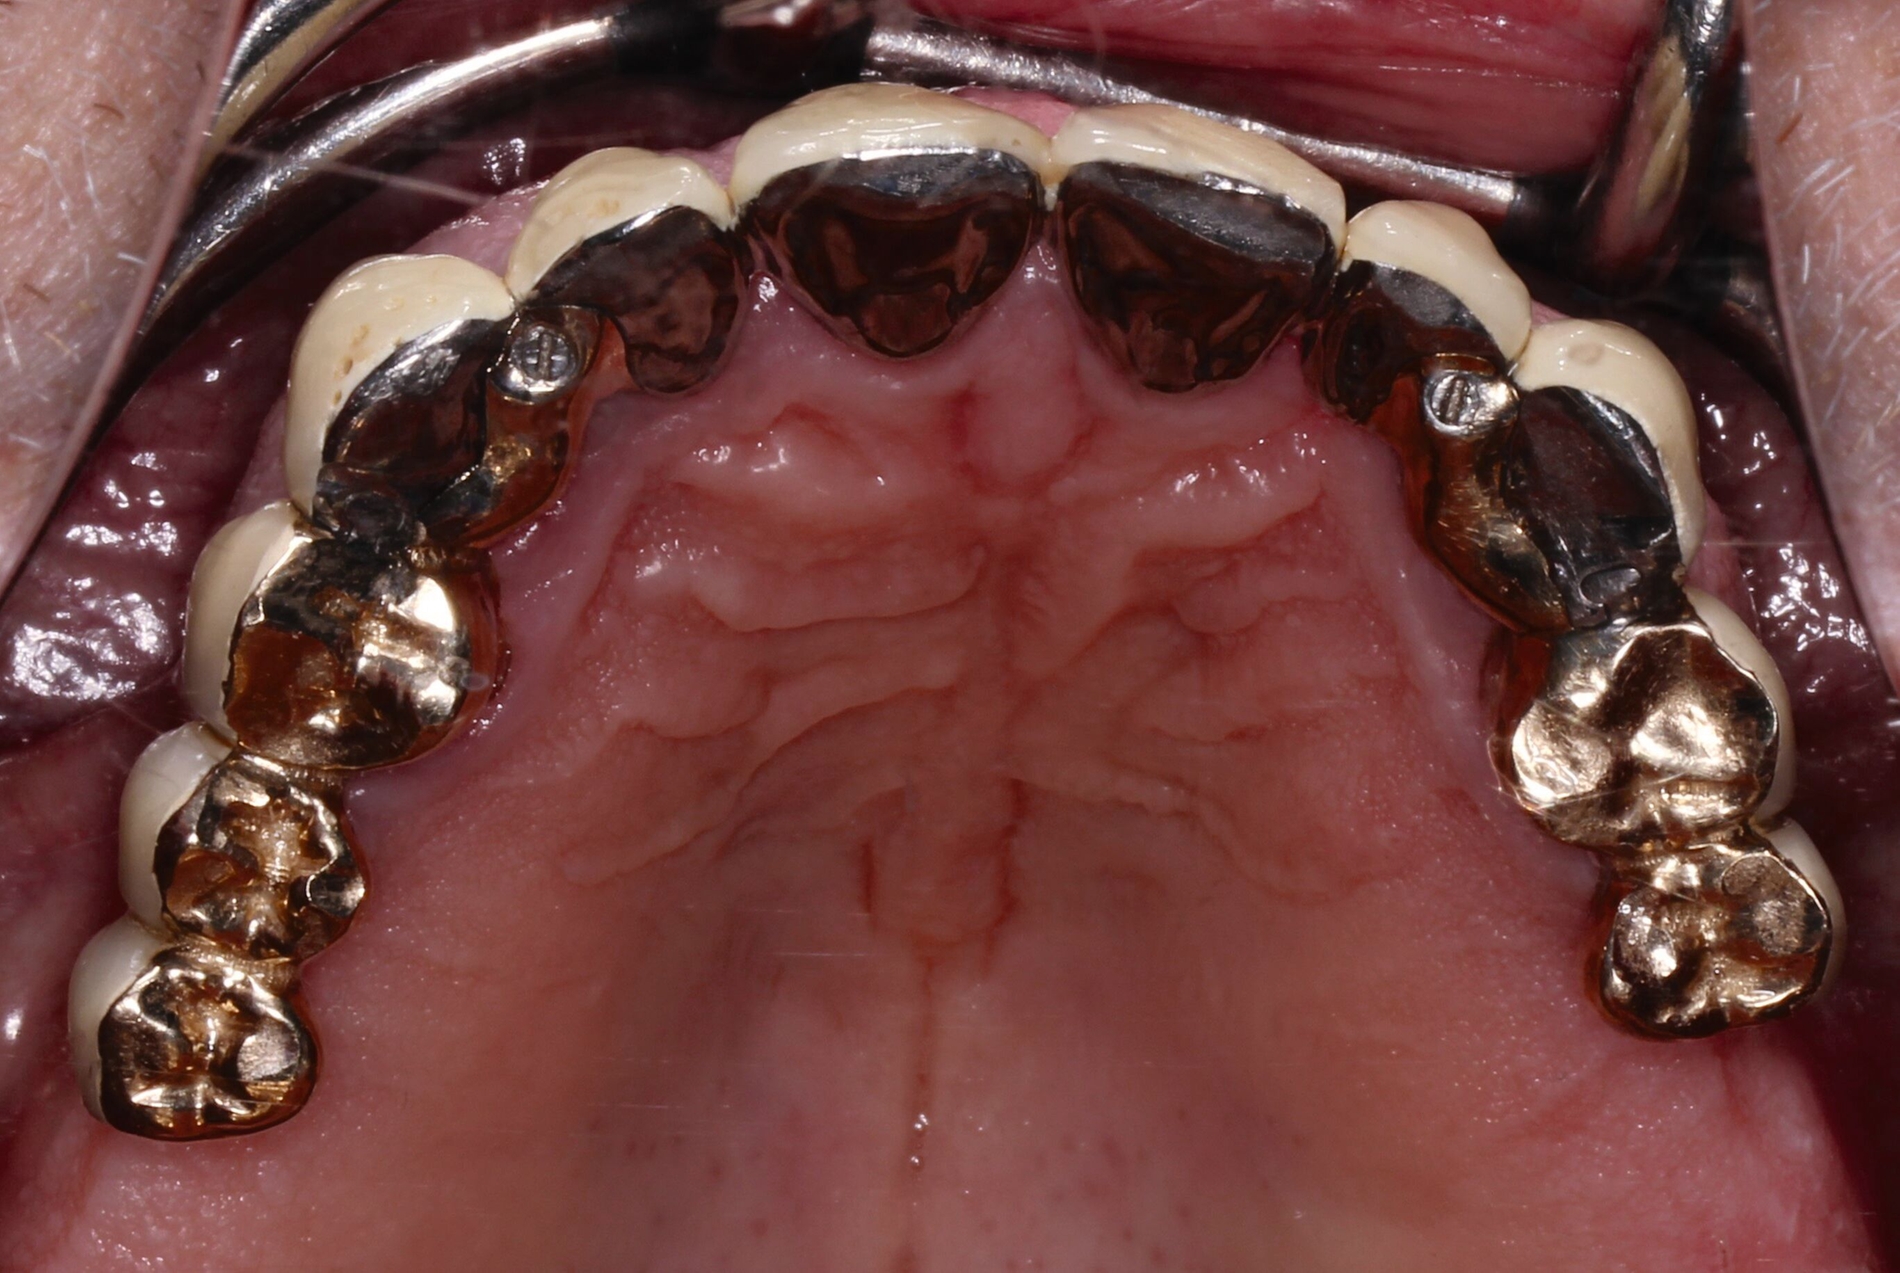

Der Patient stand unter der Dauermedikation von Metformin 500 mg, Ramipril 5 mg, Torasemid 10 mg, Metohexal 47,5 mg, Simvastatin 20 mg, Tamsulosin 0,4 mg und 3 mg Marcumar (INR 2,5–2,8) bei Zustand nach einer Bypass-Operation im Jahr 2019. Klinisch zeigten sich im Oberkiefer insuffiziente, verblockte und verblendete NEM-Kronen mit beidseitigen Gold-Extensionen distal, die über Geschiebe mit dem anterioren Anteil verschraubt waren (Abbildungen 1 und 2). Der Patient berichtete, dass die vorhandenen Kronen und Brücken 1984 eingesetzt worden seien.

Die Stümpfe wurden folglich zur Aufnahme von Teleskopkronen präpariert und mittels Doppel-Fadentechnik für die konventionelle Abformung mit dem Polyether vorbereitet. Nachdem das zahntechnische Labor die NEM-Primärteleskope hergestellt hatte, wurden sie am Patienten anprobiert und mit einem Tropfen provisorischen Zements auf den Stümpfen fixiert (Abbildung 5a), um sie anschließend in der Fixationsabformung mit abzuformen (Abbildung 5b).